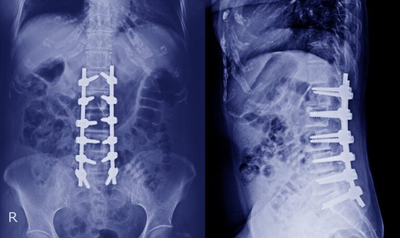

Spine surgery including Endoscopic spine surgery